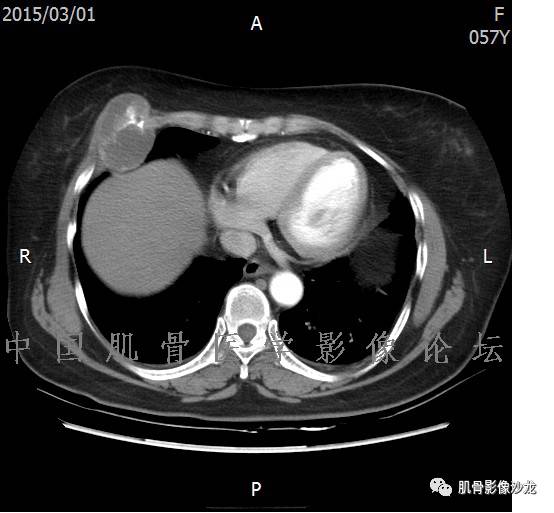

患者2月前无明显诱因下感右腿疼痛、麻木,疼痛呈持续性,发作时无法行走,休息后可缓解。当时无明显肿块,患者遂至当地医院就诊,查X片见右髂骨骨质破坏。6周前患者自觉右髋部渐大肿块,初肿块较小,后肿块逐渐增大,现肿块约12*10cm大小,有压痛。患者遂至我院就诊,查MRI:右髂骨异常信号,伴软组织肿块。ECT、肺CT未见转移。现患者为求进一步治疗,门诊拟“右髂骨肿块 ”收治入院。 患者发病来,神清,精神可,胃纳夜眠可,二便无殊,体重无明显变化。

信号 飞鹰行动:的确应该考虑软骨类肿瘤

飞鹰行动 : 软骨肉瘤内也有纤维组织的

飞鹰行动 : 第一列可以看见T2小结节样高信号,周围有纤维组织环绕

高回青 : 另外还可以见到扇贝状分叶

1、软骨肉瘤可以有膨胀性骨质破坏(病例3,4),可以有溶骨性骨质破坏(病例2),局部皮质因为破坏变薄,中断 ;

2、软骨基质T2WI高信号,软骨小叶分叶状,也就会出现高老师提到的骨内膜扇贝形压迹。一般认为骨内膜扇贝形压迹超过骨皮质厚度的2/3是软骨肉瘤在长管状骨的特征性表现。如上图。3、软组织肿块或肿胀;